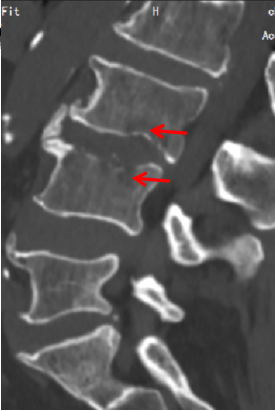

箭頭所指為患者3、4椎體,呈蟲蝕樣骨質破壞,考慮感染所致